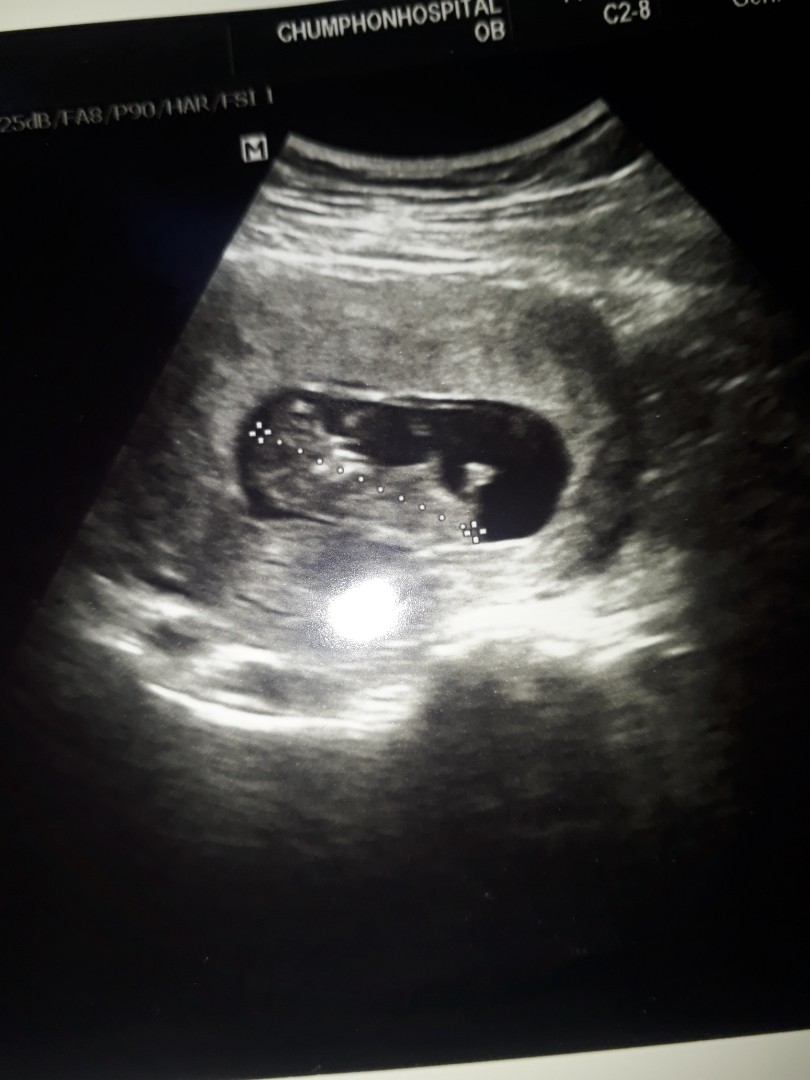

11 week

ไปอัลต้าซาวด์มาปกติเห็นแขนขาครบรึยังคะ แต่หมอก็บอกตอนนี้ครรภ์ยังน้อยอยู่(3เดือน) ไม่สามารถบอกได้ว่าครบ32 ไหม แอบกังวลนิดๆค่ะ แต่ก็คิดว่าเค้าคงยังไม่โตเหมือนที่หมอบอกมาคร่าวๆนั่นแหละ มีใครเคยซาวด์ตอนอายุครรภ์เท่ากันบ้างคะ ขอแชร์ประสบการณ์หน่อยค่ะ